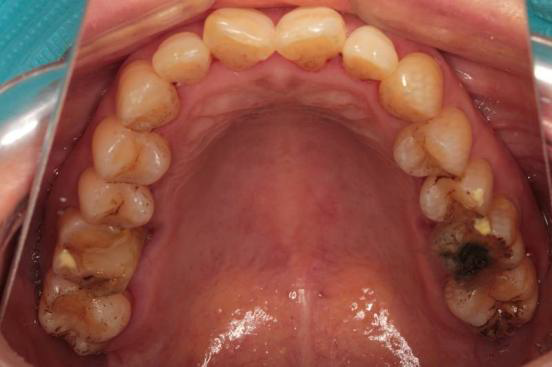

检查: 口腔卫生条件可,CI=1, DI=1,牙龈无充血肿胀,BOP(-),牙龈退缩约0.5~1mm,未探及深牙周袋,PD:3~4mm;口腔黏膜色性质正常, 舌体大小、形态、活动度正常。 36、47缺失,右侧下颌为游离端缺失,缺牙区近远中间隙及HE龈间隙可;剩余牙槽嵴吸收呈I型,高圆形;35、37牙体未见明显缺损,叩(-),松(-),46近中颊HE面有一大面积磨耗,探(-),叩(-), 松(-),上下前牙切端不同程度磨耗,并有不同程度的黄染,16远中HE面有一大面积黑色色素沉着,探(-),叩(-),松(-)